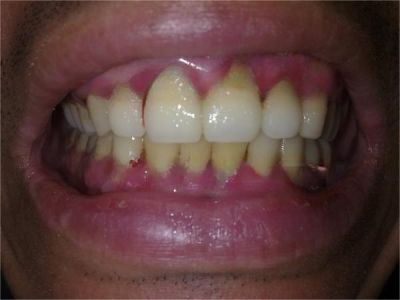

急性坏死性溃疡性龈炎症状图片

急性坏死性溃疡性龈炎起病急,病程短,常为数天至1-2周,以龈乳头和龈缘的坏死为其特征性损害,尤以下前牙多见,初起时龈乳头充血水肿,个别龈乳头顶端可发生坏死性溃疡,上覆有灰白色坏死物,中央凹下如火山口状。龈缘如虫蚀状,坏死区出现灰褐色假膜,擦去后可见出血创面。龈乳头被破坏后与龈缘成一直线,如刀切状。病损一般不波及附着龈,患处牙龈极易出血,疼痛明显并有腐败性口臭。